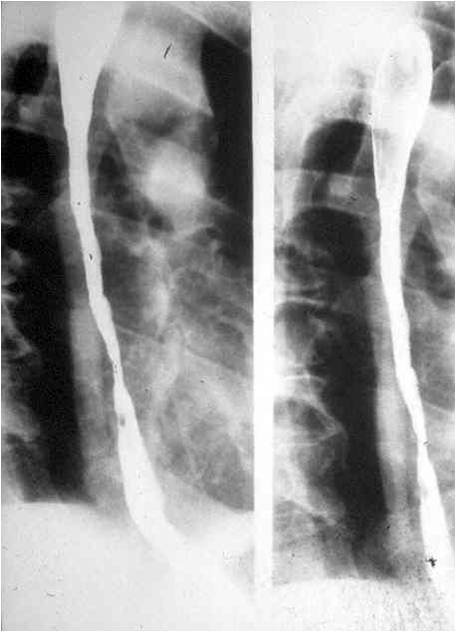

Image

Fig.1.: Normal anatomy of the esophagus

In the double-contrast esophagram the negative contrast is generated by indigestion of CO2 producing crystals. Orientation of the mucosal folds is longitudinal. The luminal diameter is 2-3 cm.